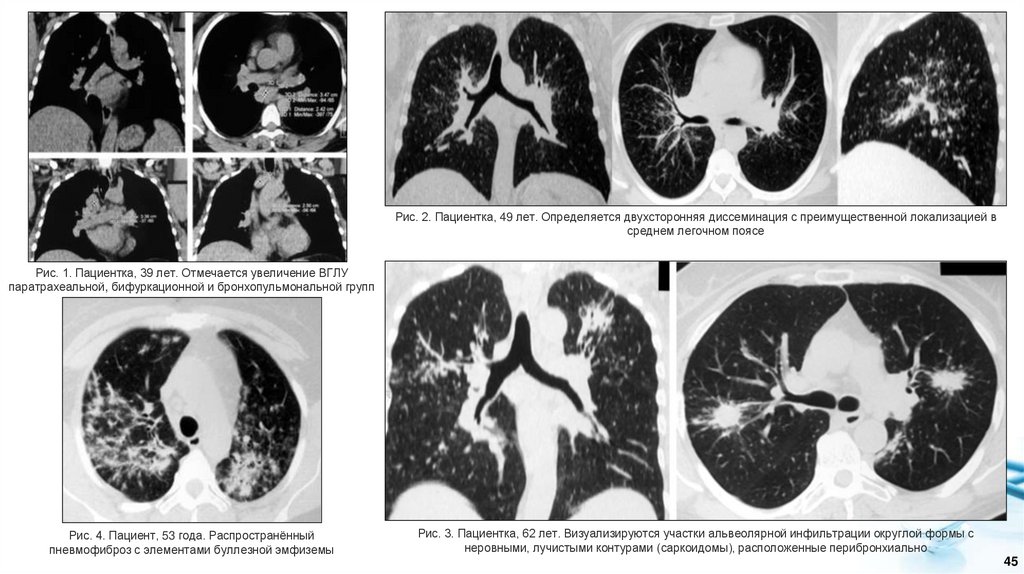

3. Методы визуализации:

• Обзорная рентгенография органов грудной клетки. На рентгенограмме пациента с внутригрудным

саркоидозом в типичных случаях обнаруживают более или менее симметричное увеличение лимфатических

узлов корней легких и средостения и/или двусторонние очагово-интерстициальные изменения в легких.

Характерно несоответствие между относительно удовлетворительным состоянием пациента и

распространенностью патологического процесса. В редких случаях возможна атипичная картина –

одностороннее увеличение ВГЛУ, односторонняя диссеминации, фокусы, участки консолидации или полости.

• Компьютерная томография легких. Для саркоидоза характерно увеличение лимфатических узлов

центрального отдела средостения, расположенных вдоль трахеи и главных бронхов, и корней легких.

Лимфоузлы переднего и заднего средостения обычно не вовлекаются в патологический процесс, что хорошо

видно при исследовании в боковой проекции. При КТ лимфатические узлы имеют шаровидную или

овоидную форму, однородную структуру, гладкие четкие контуры, без перифокальной инфильтрации и

склероза. При внутривенном контрастировании лимфоузлы равномерно и умеренно накапливают

контрастное вещество, что отличает эти изменения от туберкулеза. Нарушения бронхиальной проходимости

в результате сдавления бронхов лимфатическими узлами не характерно для саркоидоза. При значительном

увеличении лимфоузлов, приводящих к внешней компрессии бронхов, в легких крайне редко могут

появиться участки гиповентиляции и ателектаза. При длительном хроническом течении у трети пациентов в

структуре лимфоузлов появляются кальцинаты, которые имеют вид множественных, двусторонних,

монолитных, неправильной формы известковых включений, расположенных вдали от бронхов в центре

лимфоузлов. Характерным признаком саркоидоза легких являются диссеминации смешанного, очагового

и интерстициального характера с полиморфизмом очаговых изменений. При КТ множественные мелкие

очаги располагаются вдоль бронхососудистых пучков, междолевых щелей, костальной плевры, в

междольковых перегородках, вызывая их неравномерное («четкообразное») утолщение. Изменения

традиционно преобладают в средних отделах легких, часто в прикорневой области и сочетаются с

утолщением стенок сегментарных бронхов. Одним из редких проявлений саркоидоза при КТ могут быть

участки уплотнения легочной ткани по типу матового стекла различной протяженности и локализации.

Частота их составляет 18-83%. Морфологическим субстратом симптома «матового стекла» является

множество мельчайших очагов, неразличимых при КТ как самостоятельные образования или, в более редких

случаях, наблюдается истинное «матовое стекло» как проявление диффузного утолщения

межальвеолярных перегородок. Развитие фиброзных изменений при саркоидозе характеризуется

нарастанием ретикулярных изменений, формированием мягкотканых конгломератов с видимыми

просветами бронхов, располагающихся вокруг верхнедолевых бронхов, неотделимых от анатомических

структур корня. Отличительными признаками заключительной фиброзной стадии внутригрудного саркоидоза

являются тракционные бронхоэктазы и сотовое легкое в верхних долях легких в сочетании с нарушением

архитектоники легких.

44